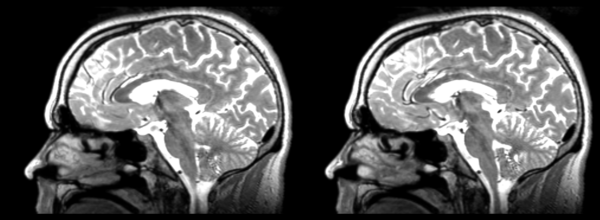

Rigid

- 53-t2 -> 31-t1 = rig1

- rig1 -> 53-t2 = rig2

Significant blurring, but every feature is in it's proper place.

Deformable B-spline

- 53-t2 -> 31-t1 = Bspline1

- Bspline1 -> 53-t2 = Bspline2

Superior frontal enlargement, odd upward shifting in rear of brain, distortions everywhere.

Diffeomorphic Demons

- 53-t2 -> 31-t1 = Demons1

- Demons1 -> 52-t2 = Demons2

Multiple deformations. Much larger ventricles. Small errors everywhere, expansions, contractions, shifts. Roughly in the same place overall.